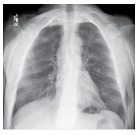

Conforme a imagem abaixo, qual nome

desta incidência?

Quanto a anatomia dos pulmões podemos

afirmar:

I - Há 2 pulmões. II - Pulmão esquerdo é maior que o direito. III - Pulmão direito é maior que o esquerdo. IV - Mediastino está abaixo do diafragma.